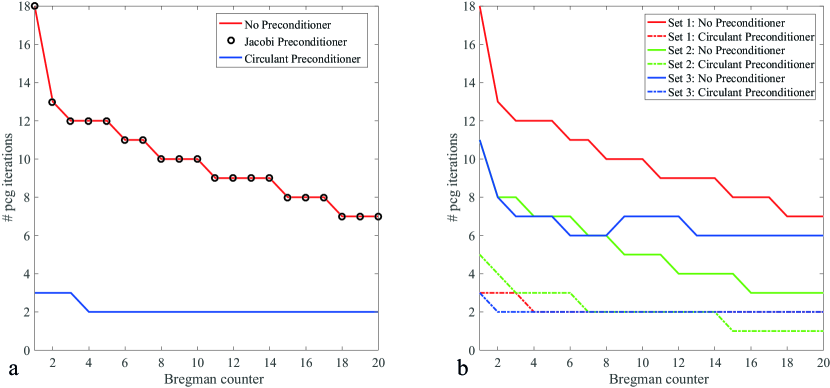

Figure 5a shows the number of iterations required for PCG to converge in each Bregman iteration without preconditioner (red line), with the Jacobi preconditioner (black circles) and with the circulant preconditioner (blue line) for regularization parameters and and a reconstruction matrix size of . The Jacobi preconditioner does not reduce the number of iterations, which shows that the diagonal of the system matrix does not contain enough information to result in a good approximation of . Moreover, it shows that the linear system is invariant under scaling. The circulant preconditioner, however, reduces the number of iterations considerably, with a reduction factor of 6 for the first Bregman iteration and a reduction factor of 3.5 for the last Bregman iteration, leading to a total speed-up factor of 4.65 in the PCG part.

The performance of the constructed preconditioner is compared for three different regularization parameters, as listed in the Method section. The number of iterations required by PCG for each Bregman iteration is shown in Fig. 5b for the three studied parameter sets. The preconditioned case (dotted line) always outperforms the non-preconditioned case (solid line), but the speed up factor depends on the regularization parameters. Parameter set 1 depicts the same result as shown in Fig. 5a and results in the best reconstruction of the fully sampled reference image. In parameter set 2 more weight is given to the data fidelity term by increasing the parameter . Since the preconditioner relies on an approximation of the data fidelity term, it performs less optimally than for relatively smaller (such as in set 1) for the first few Bregman iterations, but there is still a threefold gain in performance. Finally, there is hardly any change for parameter set 3 compared with parameter set 1, because the larger wavelet regularization parameter gives more weight to a term that was integrated in the preconditioner in an exact way, as for the total variation term, without any approximations.